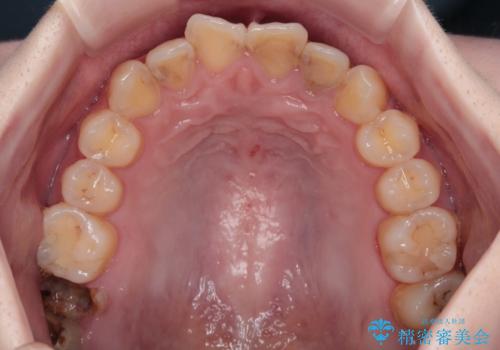

- 過去の歯医者通いの恐怖から虫歯を放置してきたものの、一大決心して来院された患者様です。

神経組織の失活している歯や歯根だけが残っている歯などがあり、全体的に歯石も多く付着している状態でした。

まずは歯石除去とブラッシング方法などの衛生指導を徹底的に行って口腔内環境を改善し、汚れの溜まりやすくなっている親知らずは全て抜去することとしました。

口腔内の環境が大きく改善し、現在はご自身のプラークコントロールにより良い状態が維持できるようになりました。